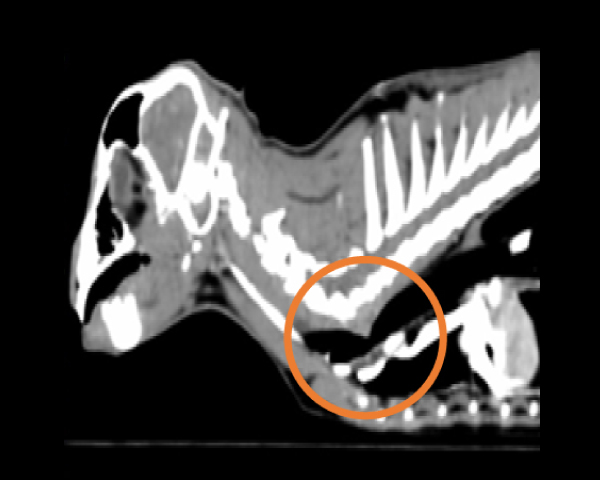

無麻酔CT検査にて異物の確定

無麻酔CT検査にて結石の個数を確認